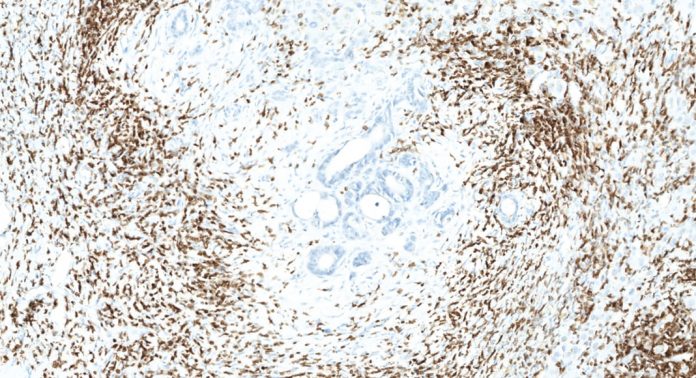

The discovery of the central role of the immune system in the battle against cancer must be accompanied by a revision of the classical tumor-centric paradigm. Perhaps one of the most urgent revisions involves an update of the current cancer classification. The American Joint Committee on Cancer/Union Internationale Contre le Cancer (AJCC/UICC)-TNM classification is the most common system for classifying the degree of tumour progression and invasion and has been used for over 80 years.1 Albeit powerful, the TNM classification proved unable to provide complete prognostic information, as clinical outcome can significantly vary among patients within the same tumour stage. A major limitation of this system is that it relies mostly on tumor intrinsic features and does not consider the effect of the host immune response on tumor development. Amongst all the proposed alternative methods, only one demonstrated higher prognostic power over the TNM classification and is based on the analysis of the tumour-associated immune response: the Immunoscore.1,4 The Immunoscore was conceived and developed by Dr Galon and his team in the light of his ground-breaking findings. Immunoscore consists in an Immunohistochemistry (IHC) – and digital pathology-based scoring system reflecting the presence of certain subtypes of immune cells, namely CD3 and CD8 lymphocytes, within specific regions of the tumour (its centre and its border, termed invasive margin).5 The scoring ranges from low (Immunoscore 0, I0) to high immune cell densities in both locations (Immunoscore 4, I4). Compared to the traditional TNM system, the Immunoscore is the only test better predicting survival for patients with non-metastatic (Stage I-II-III) colorectal cancers.1,4

This may have profound practical implications and impact. For example, in routine clinical practice, the treatment for patients with localised colorectal cancers (not involving lymph nodes or distant sites) consists in surgical removal of the tumour. However, the presence of undetected metastases cannot be excluded, even at this early stage. In fact, this might be the case for these patients (approximately 25%) having disease recurrence. This subgroup of patients could benefit from additional therapies, which could extend their life expectancy. Strikingly, whilst the current classification fails to identify this subgroup, the Immunoscore approach can. Compelling evidence demonstrated that the majority of patients with a low score experienced tumour recurrence and had a significantly lower life expectancy than patients with high score. Masterfully, by the means of the Immunoscore, digital pathology and artificial intelligence are first stepping into the emerging field of immuno-pathology.